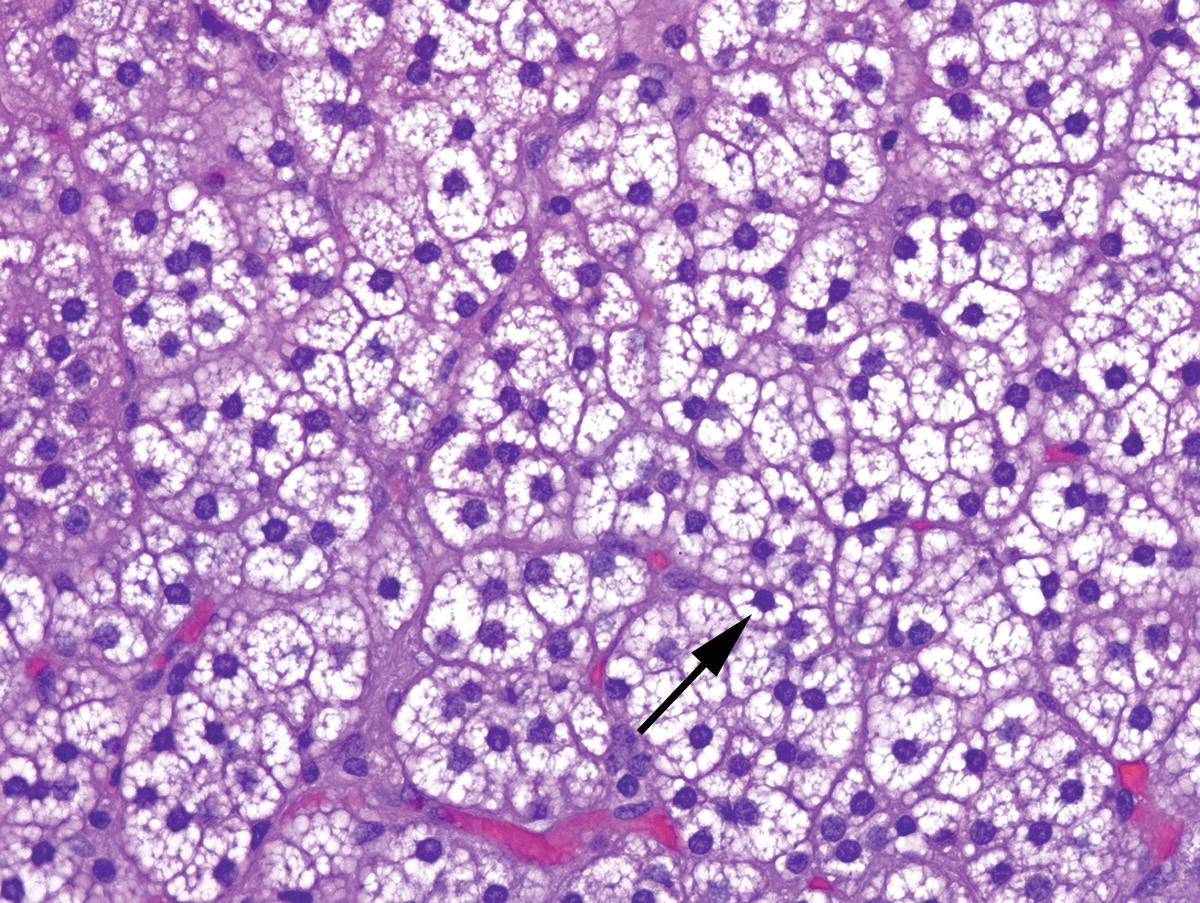

Pathology Outlines Clear Cell Sarcoma